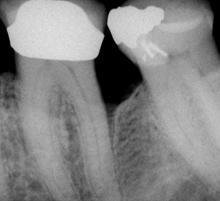

• - Fig. 1 Fig. 2 Fig. 3

• - Fig 1. Initial defect (outlined) shows as a dark area of bone loss.